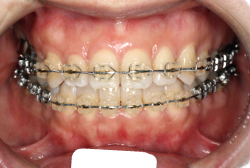

凸凹な歯並びのことを叢生といいます。矯正歯科に来院する患者様の主訴の中で、最も多いのが「配列の凸凹を真っ直ぐにしたい」というものです。歯の大きさと顎の大きさの調和がとれていないことが原因です。

凸凹を主体としたケースの場合、当院の平均治療期間は18ヶ月ですので、このケースは少し長めに経過しました。理由の一つは凸凹の程度がかなり重症だったと言うことですが、もう一つは、右下第2大臼歯が45度くらい前傾していたため、それを整直化させるために時間を要したと考えています。いずれにしても最終結果は大変よい状態と思います。

治療前は並びが乱れて見た目が悪いというのはもちろん問題ですが、歯科医学的に一番困るのは噛み合わせが悪いという点です。上下の犬歯(3番目の歯)は、上下的に離れた位置にあるため接触することができません。つまり歯としては存在していても、歯としては機能していないということです。

凸凹の強弱とは関係なく装置を最初に付けて数日は強い不快感・疼痛がありますが、数日~2週間で慣れてきます。特にこの症例のように凸凹が厳しい場合は、凸凹の歯の表面にさらに凸凹した装置が付きますので、非常に歯が磨きにくくなり虫歯や歯周病のリスクが高まりますので、歯磨き指導を十分に受けて、セルフメンテナンスに努めることが重要です。

本症例のように前歯部の凸凹が強い場合、歯間部歯肉が痩せて退縮する場合があります(ブラックトライアングル)。またマルチブラケット法全般に言えることは、口腔粘膜の違和感、金属アレルギー、歯根吸収などのリスクがありますので、事前に担当医より詳しい説明を受けて下さい。